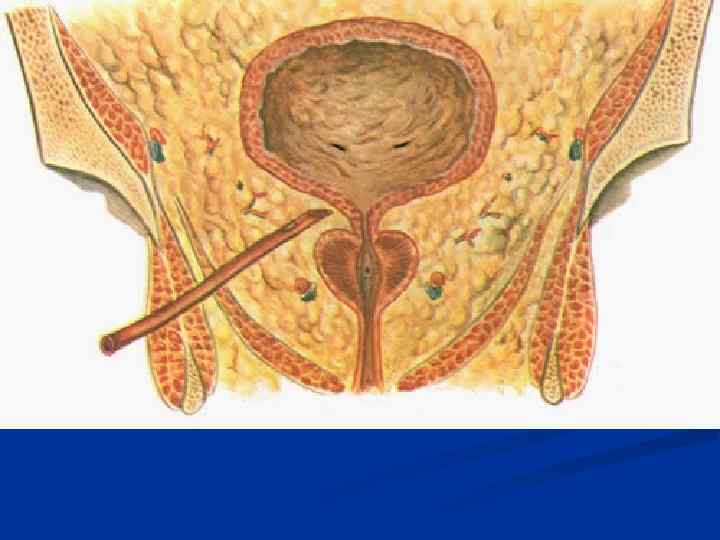

Женские половые органы, organa genitalia feminina

Женские половые органы, organa genitalia feminina